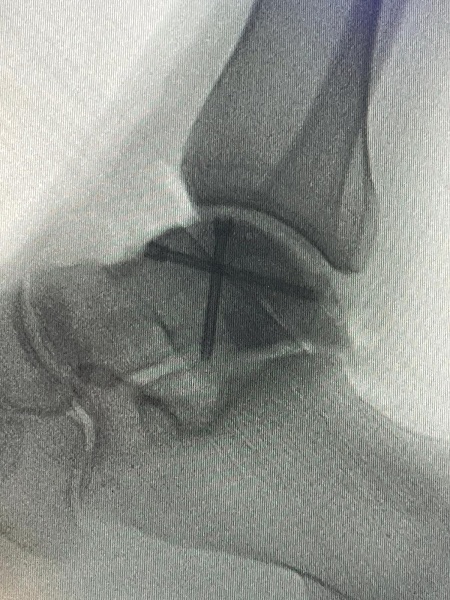

Gerçekleştirilen ameliyatla ilgili bilgiler veren Ortopedi ve Travmatoloji Anabilim Dalı Öğretim Üyesi Doç. Dr. Aziz Atik; “Lenf kanseri olan 21 yaşındaki hastamız lenf kanseri tedavisi görerek sağlığına kavuşmuş ancak ilerleyen zamanlarda aldığı tedavilerin yan etkisi olarak ayak bileği kemiğinde çürüme meydana gelmiş. Bize başvuran hastamızın eklem yüzeyi bozulmuş ve hastamız yürümekte zorlanıyor, topallıyordu. Büyük bir lezyonu olan hastamıza büyük lezyonlarda uygulanan en iyi tedavi yöntemi olan ve nadir olarak yapılan bir ameliyatla kadavra donörden kemik ve kıkırdak doku nakli gerçekleştirdik.” ifadelini kullandı. Ülkemizde kemik ve kıkırdak bankası olmadığının altını çizen Doç. Dr. Aziz Atik, yurt dışından bir donör bulmak için çalışmalar yaptıklarını ve yurtdışından kemik bulunduğunda ivedi bir şekilde ameliyatı gerçekleştirdiklerini söyledi. Ameliyatın son derece başarılı geçtiğini belirten Doç. Dr. Aziz Atik, güzel bir eklem düzeyi elde ettiklerini ve ameliyatla genç bir insanın topallamadan, ağrısız yürümesini hedeflendiklerini dile getirdi.